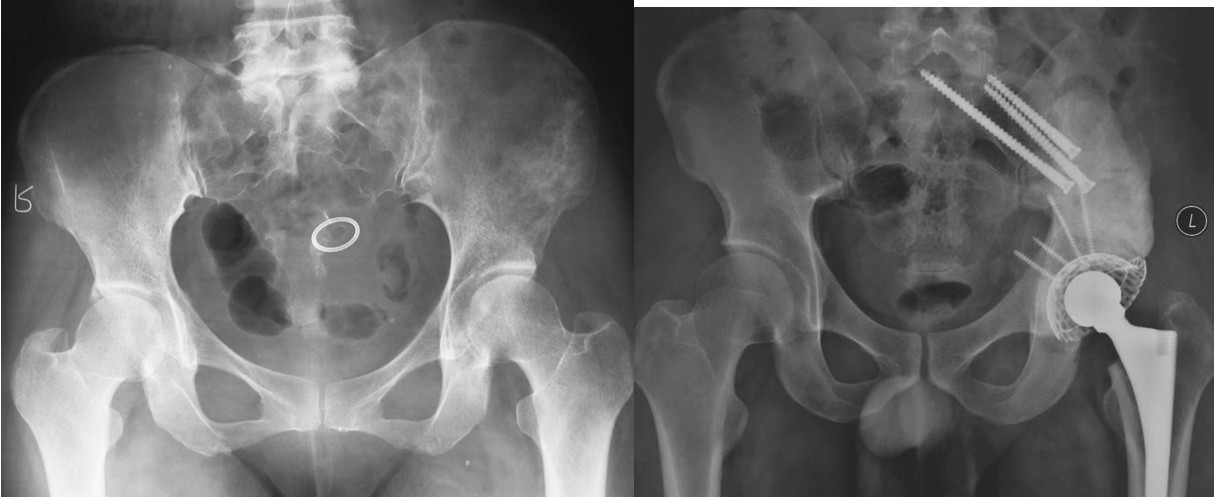

图5,男,69岁,肾癌髋臼转移, Harrington IV型

Ⅳ型:为了达到治愈而需要进行整块的髋臼切除。对于部分单一髋臼转移的病例,以及髋臼周围骨质破坏范围较大的病变,在广泛切除肿瘤后,重建髋关节(内半盆切除)有时较为困难。在这些病例,可以选择马鞍式假体。这种方法最开始用于全髋关节置换术后的骨缺损,后来也用于原发或转移性髋臼肿瘤的治疗。也可以选用带有固定翼,能固定于残存髂骨和耻骨支的定制型髋臼假体(7-9)。这种假体制作前通常需要进行CT模拟重建设计。固定方式常用螺丝钉和骨水泥。有时想要应用定制型假体达到理想的固定位置较为困难。对于骨盆环的完整性重建,纵向稳定是极其重要的,同时要考虑人工假体在术中的可操作性。定制型骨盆假体为非组配式,其髂骨固定螺钉是单轴向的,不能根据术中截骨情况调整假体,固定也不够牢固。 我们设计使用的可调式半骨盆假体,其髂骨固定钉改为双轴向或多轴向固定,假体与骨之间的界面为垂直压力、而非剪力,增加了稳定性,同时可以根据髂骨截骨的高度选择颈长的臼杯,利于安装和保持骨盆平衡(10)。组配式骨盆假体还考虑到骨盆纵向和侧方的稳定因素, 尽量达到恢复骨盆环连续性和稳定性的目的。对于髂骨区和髋臼上缘的骨缺损重建,钉棒系统简单,易于操作,但固定钉在骨内的应力较大,容易在负重的情况下对骨质产生切割,尤其骨质疏松的病人固定更加不稳,因此需用骨水泥加强。由于组配式人工骨盆是一个组合装置,因而体积较小,便于软组织覆盖,伤口感染率大大下降。